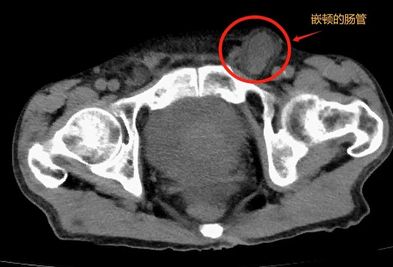

许多老年人突然嵌顿疝,普外科团队微创“修复”险为夷。 疝是一种不容忽视的疾病,常发生在早产儿、婴幼儿和体质虚弱的中老年人中。由于这些人的身体特点,他们相对更容易被疝“侵犯”。 嵌顿疝是疝气严重发展后的一种情况,危害很大。当腹腔器官疝进入时,不能自行复位, 2025-01-29